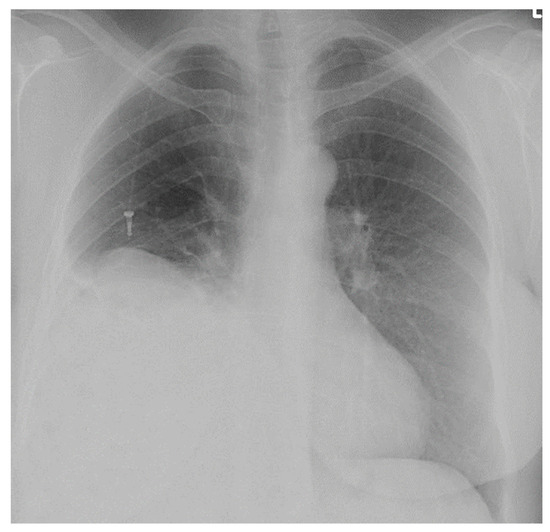

Diaphragmatic Liver Herniation after Radiofrequency Ablation of a Secondary Liver Tumor